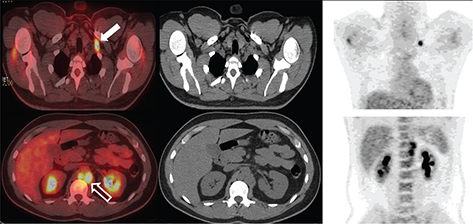

Germ cell tumors can spread via both lymphatic and hematogenous routes with frequency depending on tumor type (Figure 4 and Figure 5); for example, seminomas often spread solely via the lymphatic route whereas choriocarcinomas often spread hematogenously to sites such as lungs, liver, and brain. Sentinel node mapping is often useful for surgical excision. There are different lymphatic drainage patterns for the right versus left testicle. On the right, the main nodes are interaortocaval chain at the L2 level. For the left, the primary nodes are the left paraaortic nodes. Some crossovers can be seen in the cisterna chyli and thoracic duct, which can then spread to the mediastinal and supraclavicular nodes (23, 2628).

Fig 4

Figure 4. Lymph nodes. FDG PET/CT demonstrates hypermetabolic activity within left supraclavicular (thick solid arrow) and periaortic lymph nodes (thick open arrow). This patient was undergoing restaging for a history of seminoma. Findings on PET/CT were consistent with retroperitoneal and left supraclavicular nodal disease.